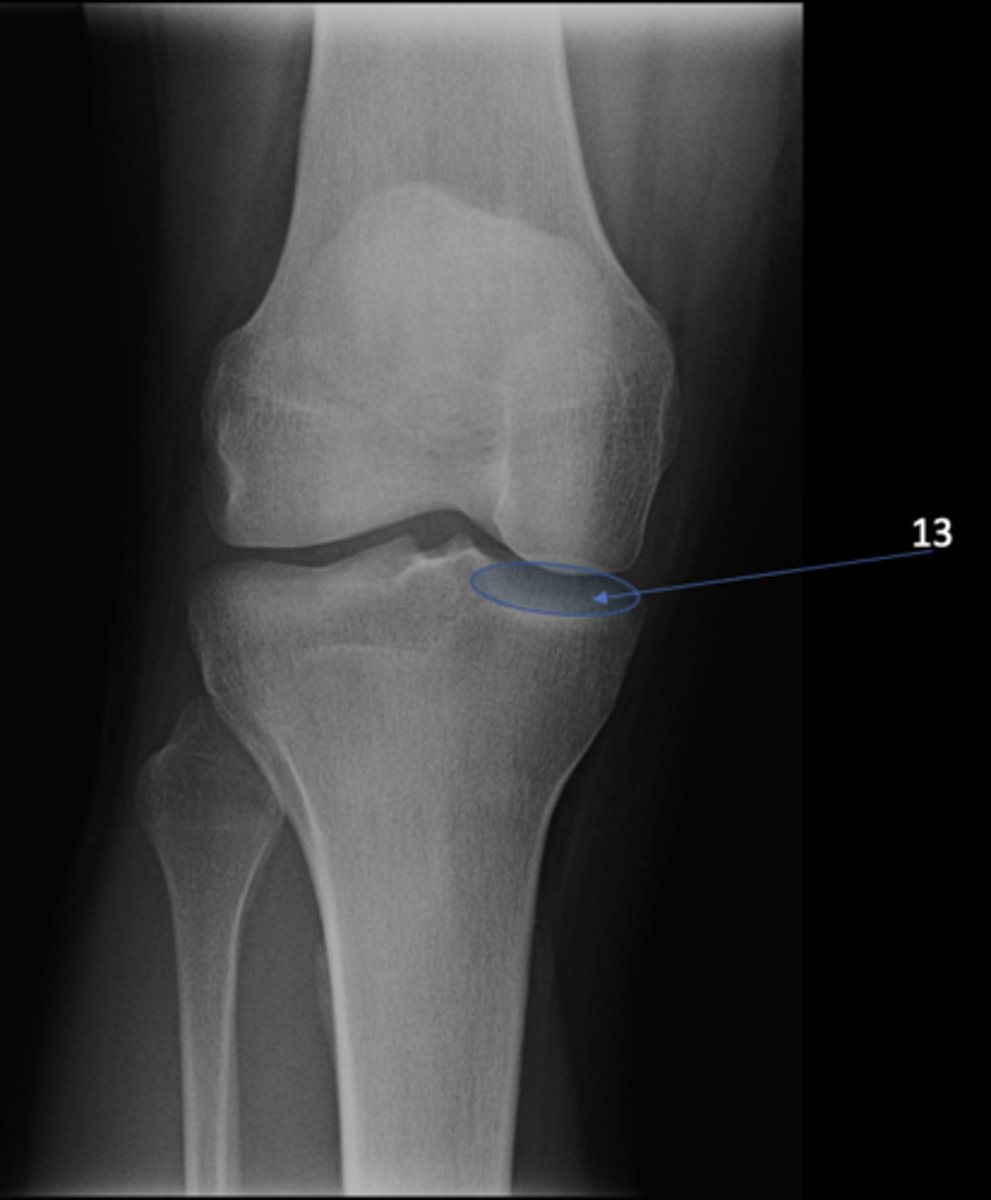

13

New cards

Left anterior inferior iliac spine

ID 13

<p>ID 13</p>

61

Medial tibial plateau